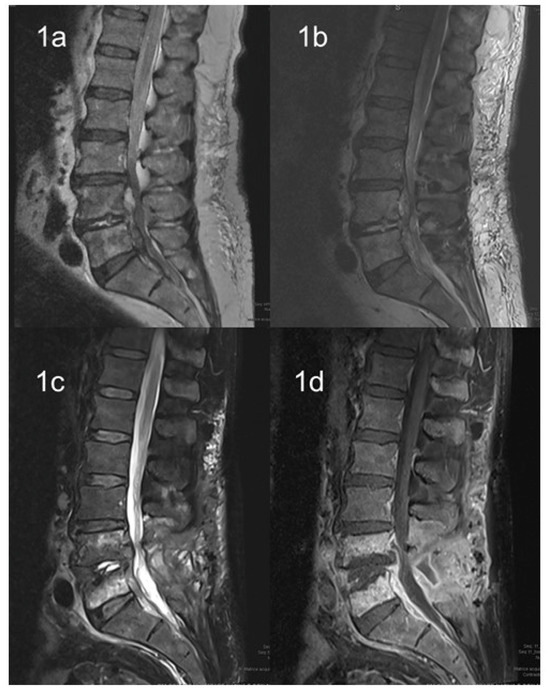

3.1. Imaging Techniques